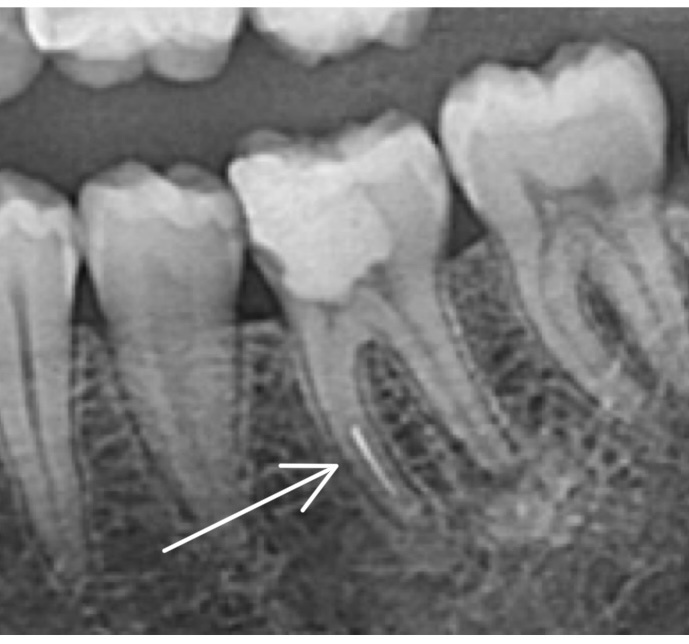

Я посмотрел у пациента в полости рта «как обстоят дела» на данный момент:

Зубик с большой дырочкой

Оказалось, что зуб болит сам по себе и при нажатии на него, имеется подвижность, примерно 2 степени. А по снимку на корнях инфекция выходит за пределы верхушки.